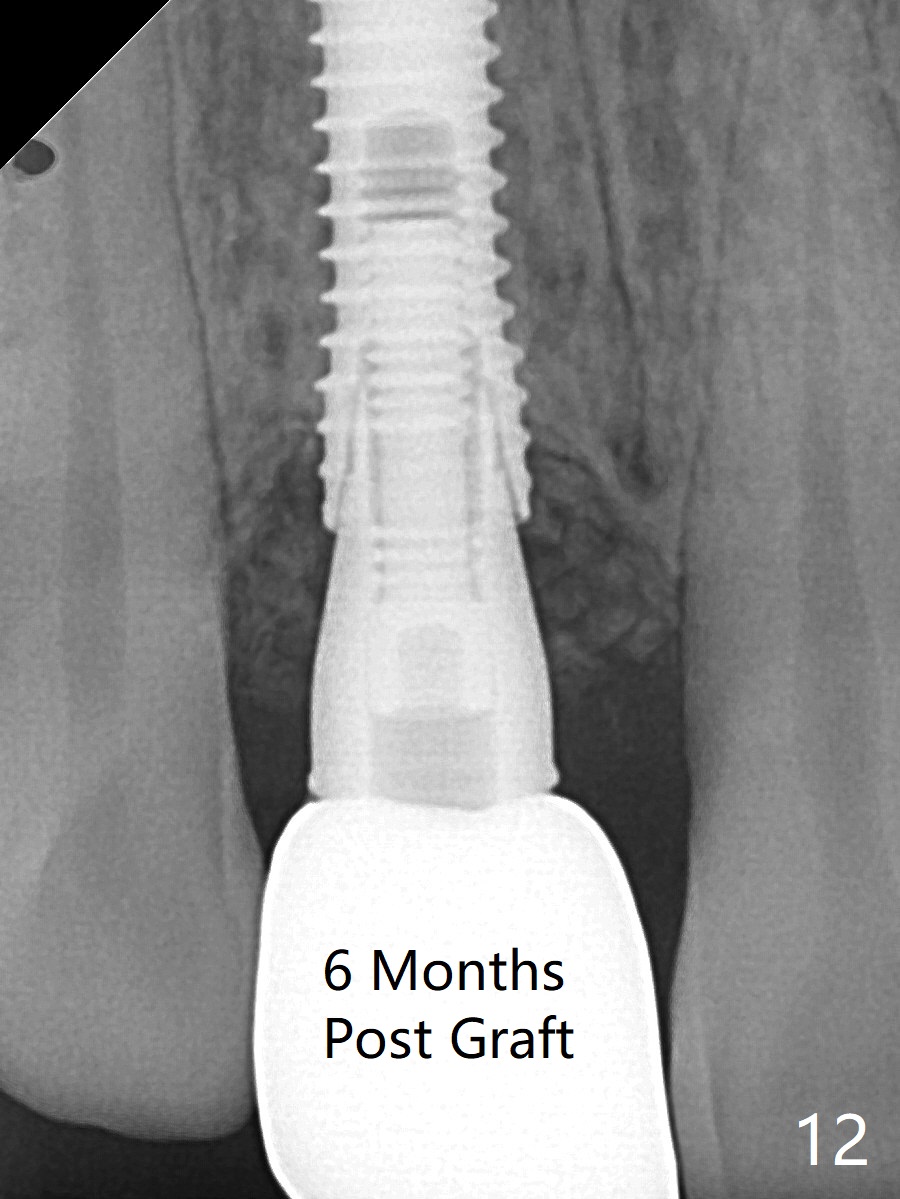

The patient returns because of purulent exudate from the buccal fistula (Fig.1 *) 1 year 9 months postop (1 year 3 months post cementation). Preop CT shows buccal thread exposure (Fig.2 arrowheads). To prevent postop gingival recession, a semilunar incision is made between the fistula and the gingival margin (Fig.3). After removal of granulation tissue (Fig.4), allograft in sticky bone form is packed (Fig.5). Following placement of PRF membrane and 6-month collagen membrane, the wound is closed (Fig.6). Since the implant (Fig.7 I) thread exposure is within bone (B) boundary (Fig.8 red dashed line), bone graft with PRF should be able to take care of periimplantitis (A: abutment). To prevent periimplantitis in similar situation, the immediate implant should be placed deep (not necessarily long, 18 mm) and narrower (3.5 mm instead of 3.8 mm). The defective buccal plate should be repaired with sticky bone and collagen membrane with incision if necessary. The wound does not dehisce 1 week postop (Fig.9) or 3 weeks postop (Fig.10, immediately post suture removal). Although bone graft seems to stay in place 6 months postop (Fig.11,12), the patient complains of bone graft expulsion sometimes. The buccal gingiva has deficiency (Fig.13). To fix it, make a remote incision (Fig.14 black line) and dissect before gingiva graft (Fig.15 dashed line). After removal of crown/abutment, the sinus track and implant surface are treated with Waterlase. A shorter cuff abutment is placed (4.5x5(4 to 3) mm) with a new provisional. The patient feels better with reduced sinus track 2 weeks postop (Fig.16).